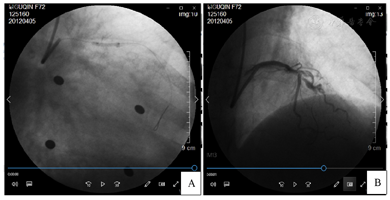

患者Syntax积分为14分,与患者及家属沟通后,计划于前降支近段及回旋支中段进行介入治疗。使用6F EBU 3.5导引导管,Runthrough NS导引导丝进入前降支远段血管,2.0 mm×15.0 mm顺应性球囊(sprinter)10个大气压(1个大气压=101.325kPa)扩张前降支近中段狭窄处。其后患者突发胸闷、胸痛、气短,继之出现三度房室传导阻滞,且无房室交界区性逸搏心律及室性逸搏心律出现而导致心室停搏。迅速进行心脏按压,静推阿托品后恢复窦性心律。造影复查,发现自左主干近段至回旋支开口处血管夹层形成,前降支及回旋支远段血管前向血流TIMI 2级(图2)。